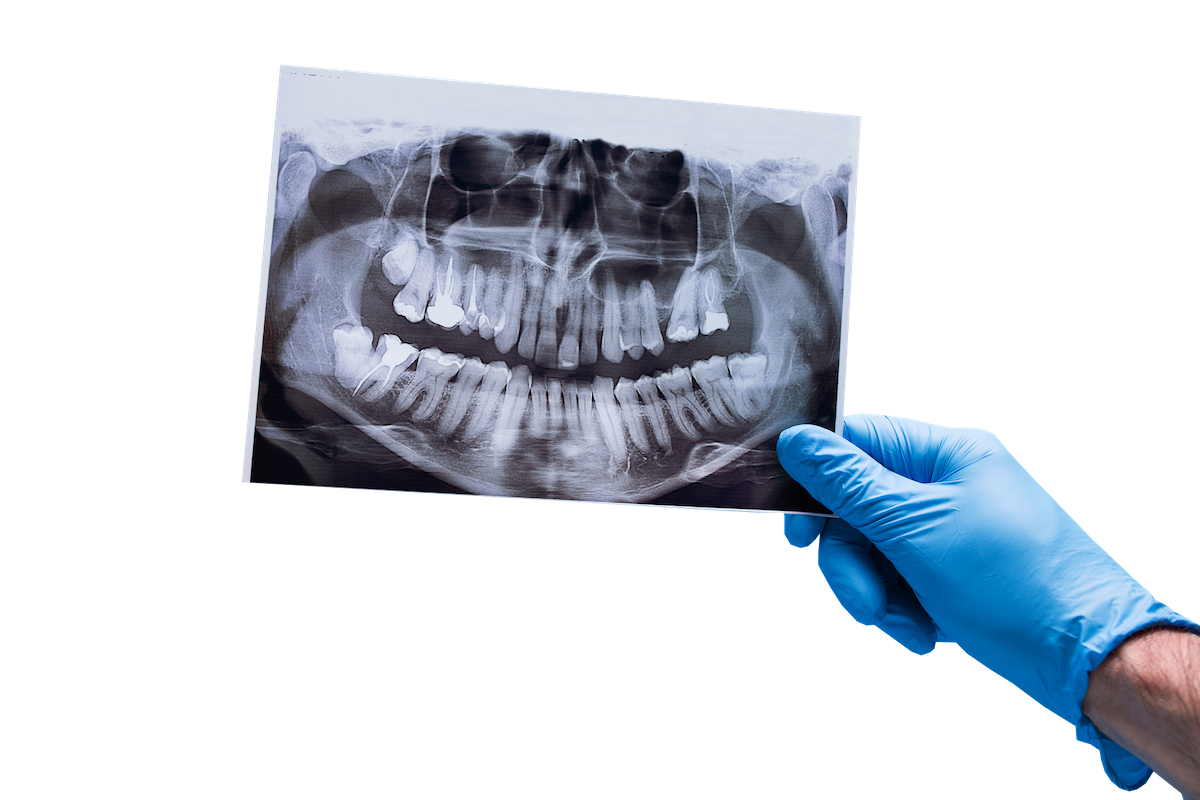

Ortopan

Ortopantomogram oz. panoramski posnetek je najpogostejše ekstraoralno slikanje zob in kosti spodnjega dela obraza v dentalni medicini.